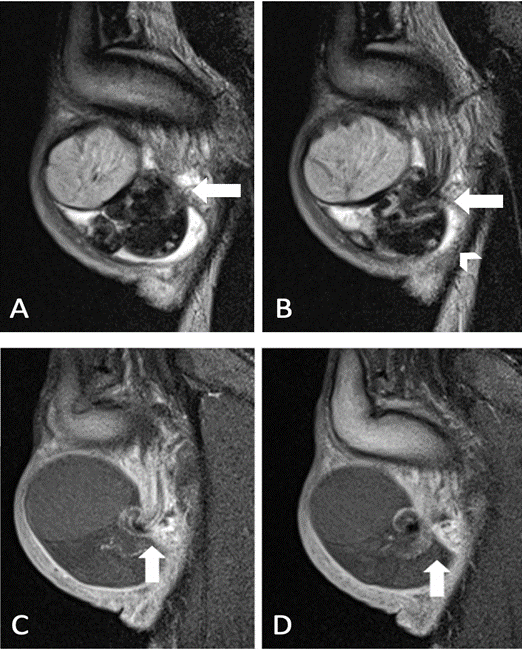

Adyacente al mismo se observa epidídimo y cordón espermático con cambio en su calibre y rotación de su eje (signo de whirlpool) por encima del ingreso a la bolsa escrotal asociado a leve hidrocele derecho y aumento de la intensidad de señal de los tejidos blandos del escroto ipsilateral (Figura 2a, 2b). Testículo, epidídimo y componentes del cordón espermático izquierdos conservados.

A) Imagen sagital secuencia T2. Cambio de calibre del cordón espermático (flecha). B) Imagen sagital secuencia T2. Signo de whirlpool (flecha) y presencia de hidrocele (cabeza de flecha). C) Imagen sagital secuencia T1. Ausencia de captación de contraste en TD, epidídimo y sector proximal del cordón espermático derechos (flecha). D) Imagen sagital secuencia T1. Continuación de la rotación del cordón espermático derecho (flecha). Origen: Servicio de Diagnóstico por Imágenes. Hospital Italiano de Buenos Aires. Buenos Aires, Argentina. 2021.

Figura 2a Comparación de imágenes sagital T2 y T1